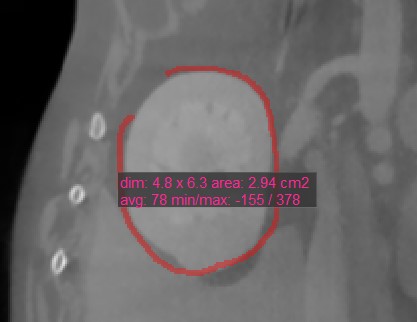

Polygon¶

Users can create, measure and mark custom rounded areas on the active image slice by using the Polygon tool.

Select the Polygon tool and assign it to one of the available mouse buttons. Start the measurement by placing points on the active image slice. As the user places the points, the software automatically connects them

and creates the rounded shape.

Complete the measurement by manually closing the path, or double-click when placing the last point to automatically close it. All available measurement values are displayed alongside the measurement.

Modify the marked area by moving one of the points describing the shape using the Default tool.